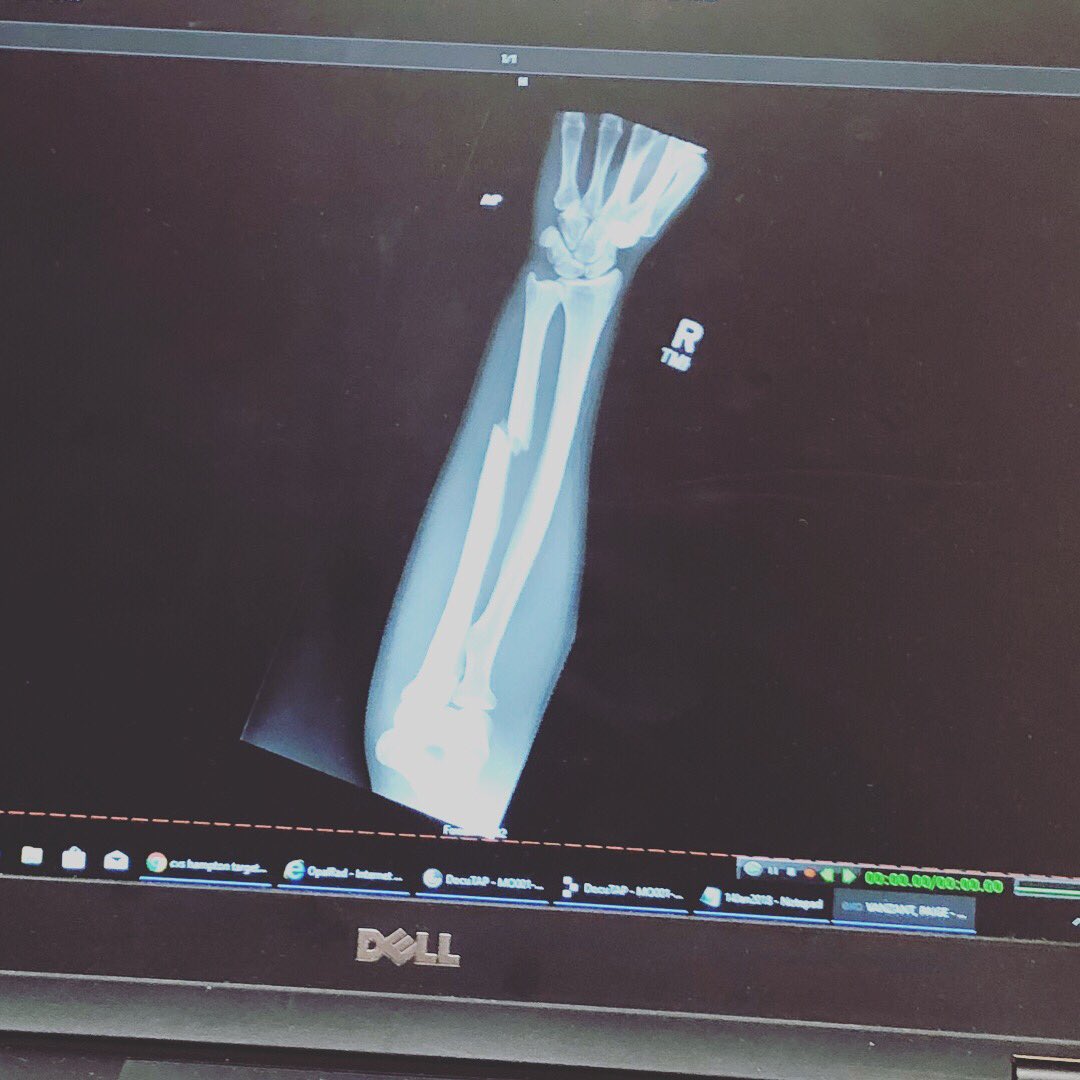

Пейдж Ванзант сломала руку во время боя с Джессикой-Роуз Кларк

Фото instagram.com/paigevanzantufc

Боец наилегчаейшего веса UFC Пейдж Ванзант сломала руку во втором раунде боя против Джессики-Роуз Кларк.

Проклятый бэкфист», – написала Пейдж в инстаграме и выложила фото рентген-снимка.

Перелом случился во время удара «бэкфист» – Ванзант попала предплечьем сопернице в лоб.